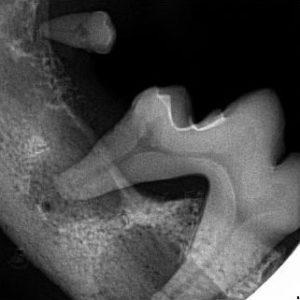

0620622001761159803.jpgEmmie is a 6 year old sweet, fluffy Maltese. She presented for her dental cleaning because owner noticed blood from her mouth. However, Emmie was still eating well at home.

On initial oral examination, Emmies teeth were thickly coated in plaque and tartar (calculus) with one painful, potentially infected tooth. After anesthetic induction and a full oral examination including dental radiograph, more than 25% of her teeth had deep infection including tooth root abscess. Large molars and multiple premolars had tooth root abscess which we did not expect from her daily behavior and awake oral examination.

I did not report any discomfort, trouble eating, no crying for pain at home.

For infection this severe, pain levels, discomfort, and systemic bacterial infection risks are very high for the pet. Extractions, some root planning and subgingival antibiotic gel application were performed. Emmie is feeling great after this major treatment.